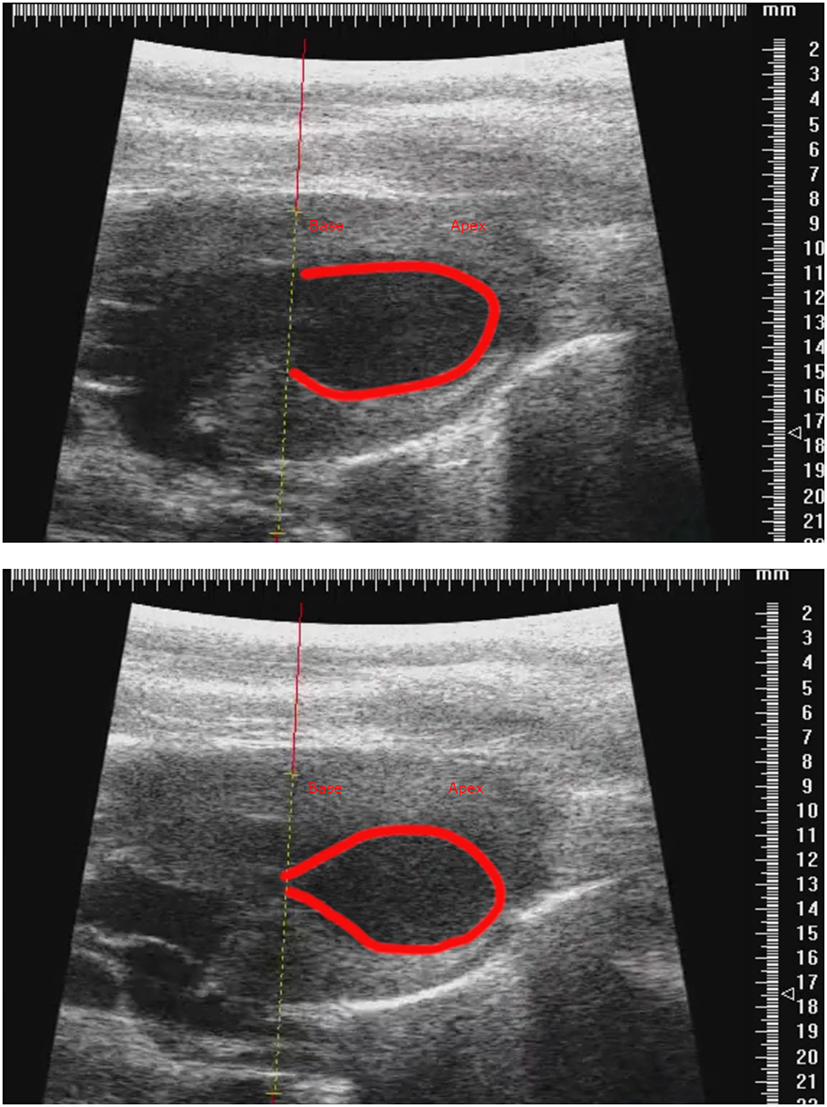

We noticed that after isoprenaline administration, animals tended to increase their body temperature, and after discussion between the two groups we determined that allowing the development of the natural transient isoproterenol-induced hyperthermia was essential for the consistent induction of TTS-like contractility in this animal model (Figure 6). Groups wishing to replicate this TTS model should pay close attention to body temperature and allow moderate hyperthermia to occur.

Figure 6

Representative parasternal long axis B-mode images of end-diastole (top) and end-systole (bottom) after induction of TTS-like contractility (base: left; apex: right), with trace (red line) drawn around endocardial border. Scale in mm.